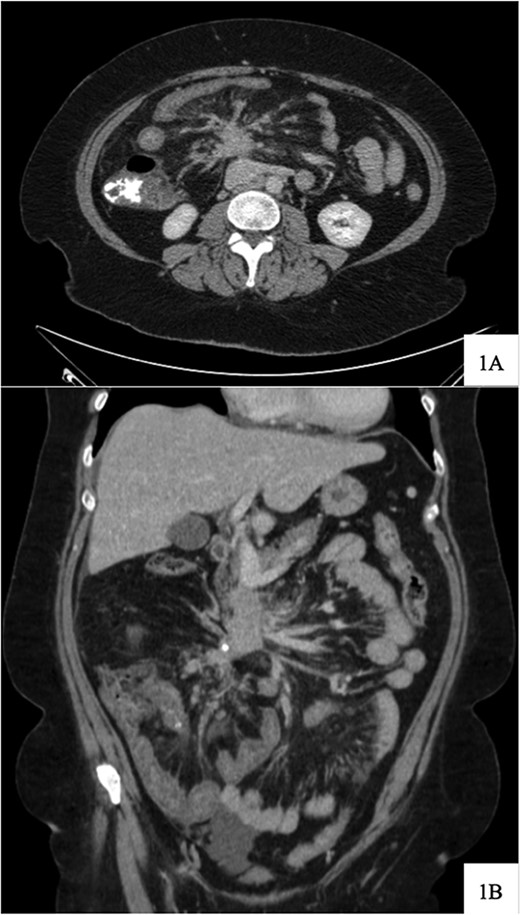

Regarding her oncologic history, she was diagnosed with NET in October of 2017 when a computed tomography (CT) scan performed for intermittent abdominal cramping and diarrhea revealed a mass near the third portion of the duodenum and the root of the mesentery (Fig. 1). Biopsy of the mass revealed a well-differentiated NET. Further work-up with DOTATATE positron emission tomography (PET)/CT revealed a small bowel primary likely emanating from the terminal ileum as well as multiple lesions in the neck, chest, and liver (Figs 2 and 3). The periduodenal mass intimately involved the root of the mesentery, SMA, and SMV. She was initially treated with Lanreotide for many years with close monitoring and later underwent systemic treatment with Lutathera, a Peptide Receptor Radionuclide Therapy, from April 2020 to November 2020. She subsequently resumed Lanreotide in December of 2020, which she was on at the time of admission. Her disease remained largely stable on imaging over the next three years; however, her symptoms had been worsening over the few months leading up to her presentation.

DOTATATE positron emission tomography-computed tomography scan at time of diagnosis in November 2017 revealed a small bowel primary tumor in the right lower quadrant consistent with terminal ileum (A) as well as the periduodenal mass near the root of the mesentery (B). Coronal reformatting redemonstrates the primary tumor (C) and mesenteric mass (D).

DOTATATE positron emission tomography-computed tomography scan revealing extent of metastatic disease.